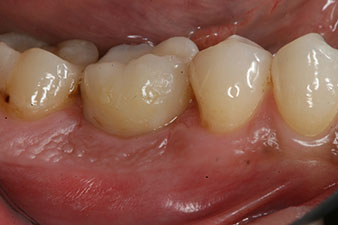

measuring probe

Fig. 6: Ten weeks later the gingiva former, which was screwed in place after placement of the implant, can be removed. In the linguo-buccal direction the ISQ value was virtually unchanged at 63 (measuring probe in proximity at a distance of 2-3 mm).

The implant was uncovered two months later and a gingiva former was screwed in (no picture).

After healing of the soft tissue, the implant stability was measured again before delivery of the prosthetic restoration.

Both values were virtually unchanged and were between the medium and the high range – where the lower value is always used as the reference value that determines the treatment.

Therefore, successful osseointegration and adequate biological stability could be recorded, which enabled an impression to be taken in the same session.